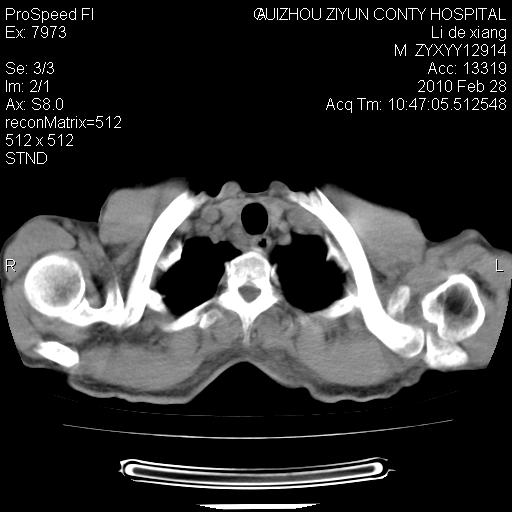

标题: CT24776:男 71Y 咳嗽咳痰胸痛两月,伴声音嘶哑。 [打印本页]

患者有声音嘶哑,若时间长了,没改变,喉镜检查无异常,可考虑左侧喉返神经受累,因为:左侧喉返神经绕主动脉弓或肺动脉韧带的主动脉端,沿气管与食管之间的沟上行至颈部.

支持肺癌.